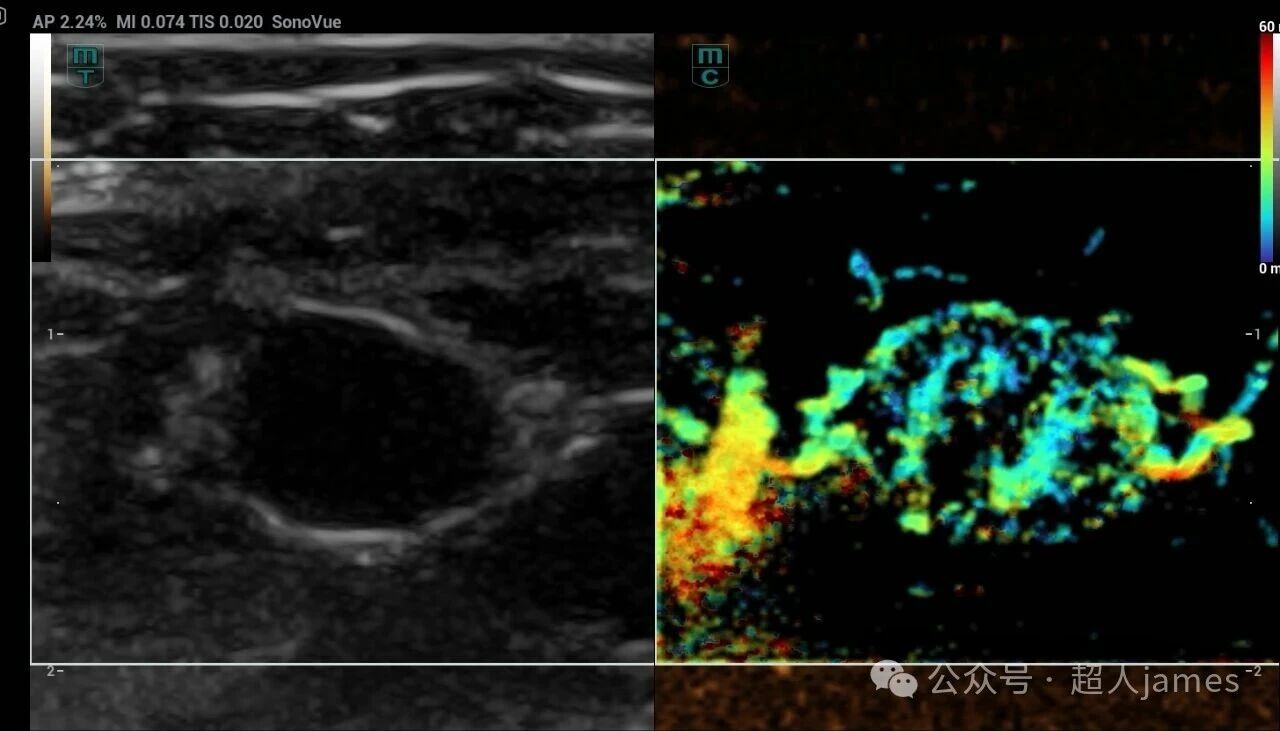

甲状腺微小癌也要警惕颈部淋巴结的转移

甲状腺微小癌也要警惕颈部淋巴结的转移,迈瑞超声

来源微信公众号“超人jams”